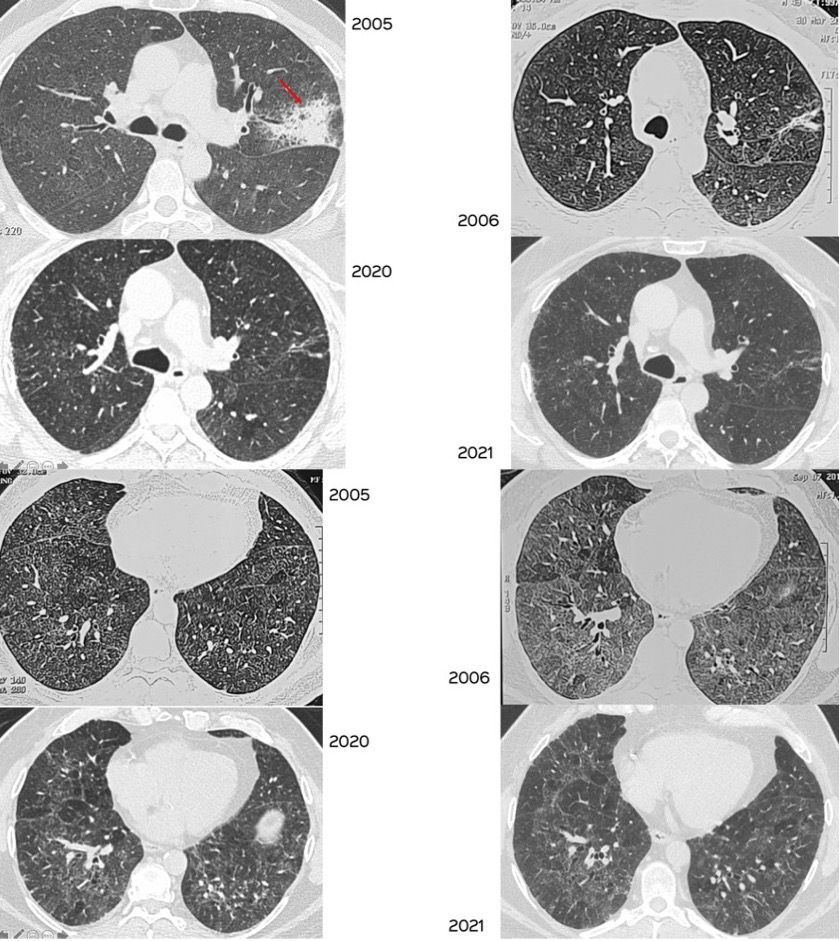

Case 29: The Slow Long Burn of Sarcoidosis Paid Members Public

The changing patterns of disease over 16 1/2 years in this patient with biopsy proven sarcoidosis